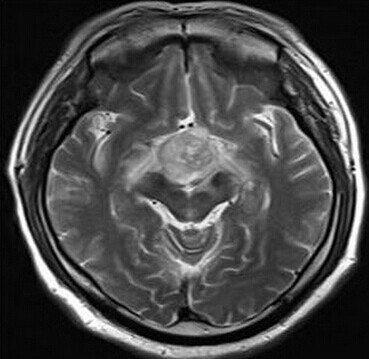

患者:男,50岁,记忆力下降1月余,双眼视力下降,反应减慢。

【正确答案】D 胶质瘤(第三脑室脊索样胶质瘤)

第三脑室脊索样胶质瘤的特征性表现是:

(1)见于成人,边界清楚,位于第三脑室前部;

(2)T1WI上为低信号,T2WI上呈明显高信号;

(3)增强后明显强化;

(4)肿块累及视交叉及下丘脑,但不浸润周围脑实质。